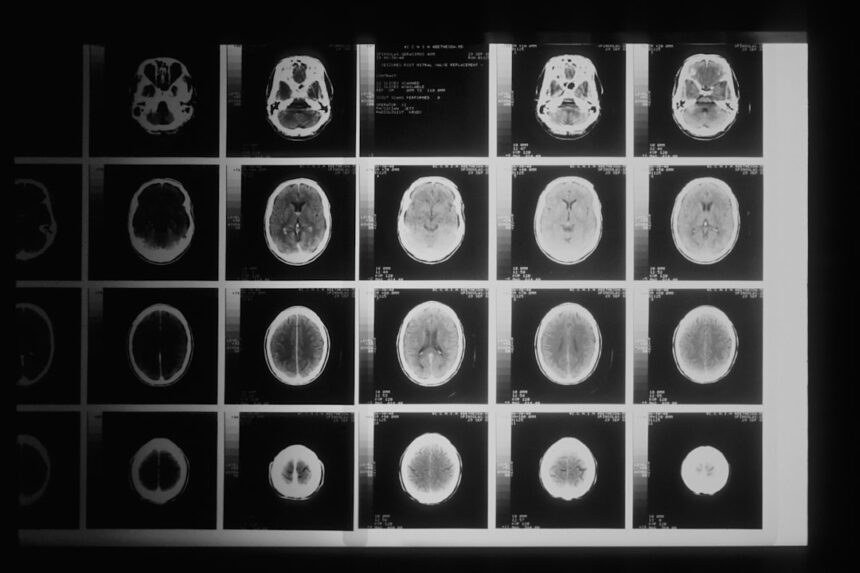

- The study used advanced imaging techniques to observe changes in brain regions linked to emotion regulation.

Recent advancements in neuroscience have provided valuable insights into the effects of emotional suppression on brain activity. A groundbreaking study utilizing brain scans has shed light on how suppressing emotions can alter the way your brain functions. This research aimed to explore the neural mechanisms behind emotional regulation and the consequences of suppressing feelings.

By examining brain activity during emotional suppression tasks, researchers have uncovered significant findings that could reshape our understanding of emotional health. In this study, participants were asked to engage in tasks that required them to suppress their emotional responses while viewing emotionally charged images. The use of brain imaging technology allowed researchers to observe real-time changes in brain activity as participants navigated their emotional landscapes.

During the experiment, participants were subjected to a series of emotionally evocative images while their brain activity was monitored using functional magnetic resonance imaging (fMRI). This non-invasive technique allowed researchers to observe changes in blood flow within the brain, indicating areas of heightened activity. Participants were instructed to either express their emotions or suppress them while viewing these images, creating a controlled environment for analyzing the effects of emotional suppression on brain function.

Recent studies on brain scans have shed light on the mechanisms of emotional suppression, revealing how our brains respond when we try to hide our feelings.